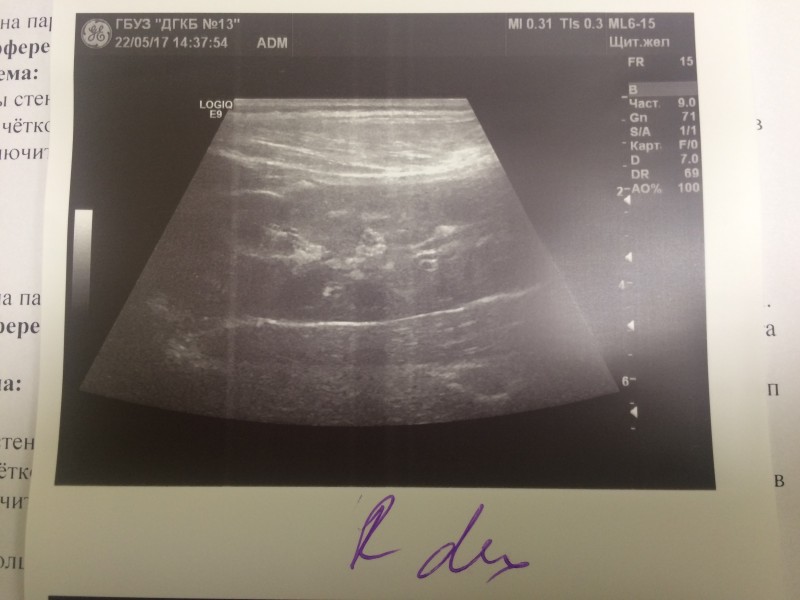

Пробегали от участковых врачей, до специалистов в Филатовской. Пока бегали, сдвали постоянно анализы и делали УЗИ. Итоги не ясны.

ещё. А файлы .pdf не могу выложить - пишет, недопустимый формат. Там анализы крови и мочи: 22/04/17 - белок в моче - 0,164 24/04/17 - белок в моче - 0,265 27/04/17 - клинический анализ крови: Нейтрофилы(общ.число), % 38.3, Лимфоциты, % 50.8, креатинин 51, мочевина 3,6

У дочки всё в порядке. Возвращаюсь к истории сына. Все анализы в норме, но одна киста выросла до 4 см в диаметре. Специалисты Филатовской больницы решили её склерозировать, учитывая удобное прилежание. Назначили госпитализацию на 4 февраля. 5-го КТ перед операцией, потом сама операция. Надеются убирать "проколом". Интересовался ваптанами. Ценник во всех странах отличается на 1-2 Евро... Неподёмный пока для нас, учитывая, что и "побочка" у препаратов есть, не кислая.

Операцию временно отложили на пару дней. По результатам КТ решили две кисты склерозировать после пунктирования, а одну иссекать лапороскопически.